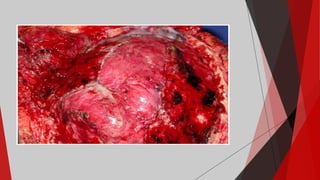

AVC Hemorrágico

É o acidente vascular cerebral menos

comum presente em cerca de 20% dos casos,

mas não menos grave. Ocorre pela ruptura de

uma artéria ou vaso sanguíneo intracraniano. O

sangue em contato com o parênquima nervoso

tem ação irritativa. Além disso, a inflamação e o

efeito de massa ou pressão exercida pelo

coágulo de sangue no tecido nervoso prejudica e

degenera o cérebro e a função cerebral.

São dois tipos:

 Hemorragia Intraparenquimatosa: ocorre por ruptura

dos aneurismas de Charcot-Bouchard, pequenas formações

saculares das artérias cerebrais na transição da substância

branca com o córtex cerebral que se formam pela hipertensão

arterial descontrolada ou não tratada.

 Hemorragia Subaracnoide: ocorre por sangramento de

aneurismas cerebrais (defeito ou formações saculares das

artérias) no espaço licórico ou subaracnóideo. Eles tem

provavelmente origem congênita.